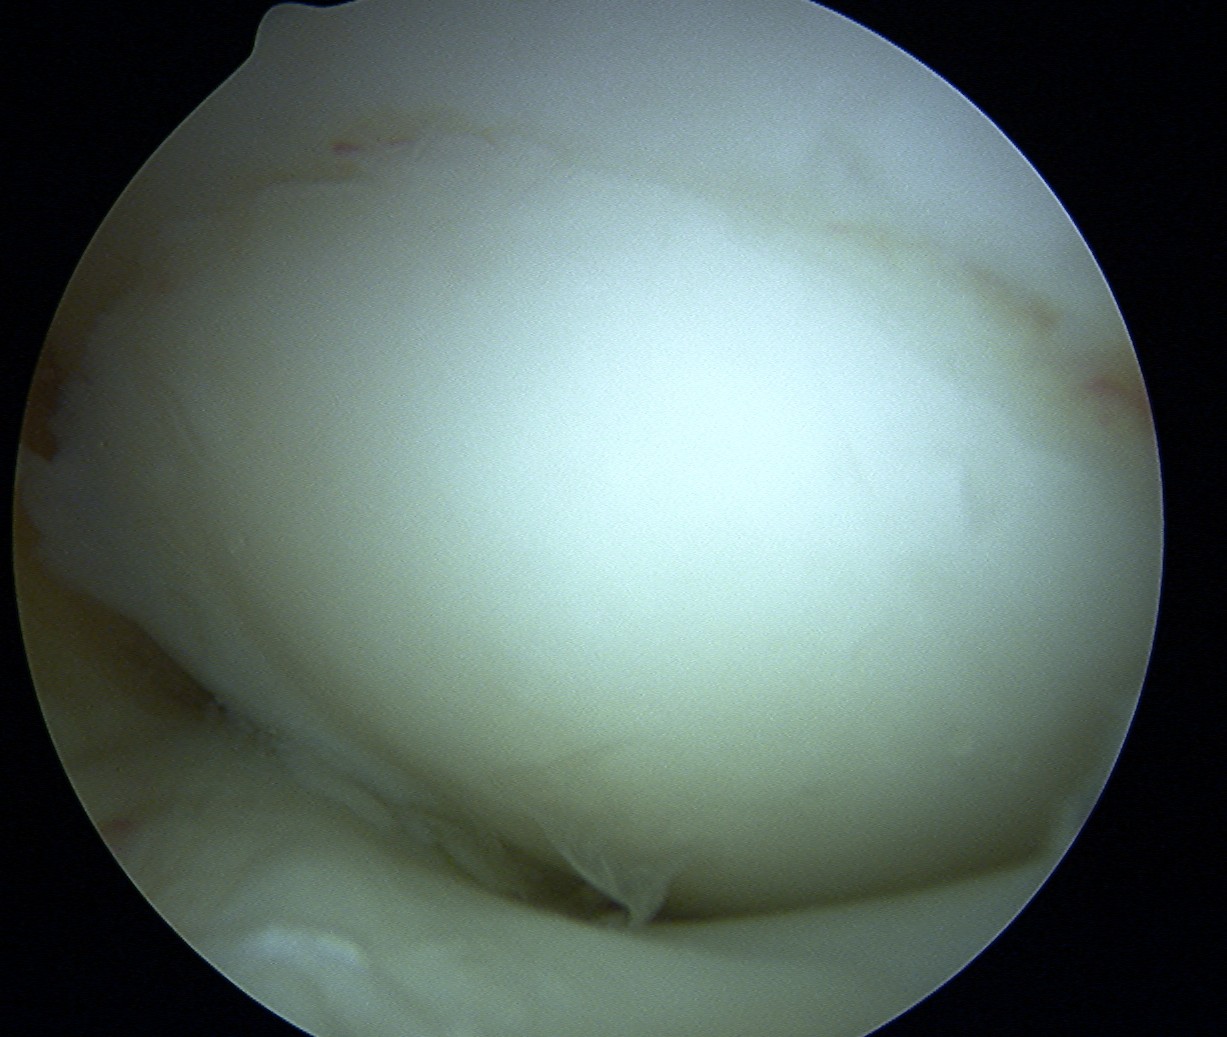

In a stage 1 lesion there is no cartilage breach

- the MFC / LFC looks normal

Cartilage intact on arthroscopy